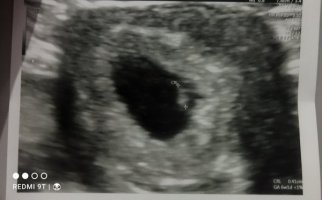

Admin inanın ne yaptım anlamadım ilk paylaştığım görüntü arkadaşımın yanlış oldu silmeyi de inanın bilmiyorum benim görüntü bu karından incelermisiniz lütfen

Hayatım tam resimde bakacağım yer parlamış bir şey göremiyorum başka resim yüklemen mümkün olur ise değerlendirmek isterim.

Suda var benim elim titriyor galiba netlestiremiyorum. Aslında şuan çok net fakat yükleme esnasında mi bulaniklasiyor anlamadım.

Selamlar, malesef üzerinde tahmin yapılamayacak kadar kötü, ilerleyen zamanlarda yenisi gelir ise atarsınız. Sevgiler. ( bulanık anlaşılmıyor )

Aslında gerçekten insan çok heyecanlaniyor ilk gebeliğim arkadasim geçen hafta bır guruba yazmış bende merak ettim tabi yinede en iyisini Allah bilir fakat yine insanı tatlı bir merak sarıyor teşekkür ederim şimdiden canım.